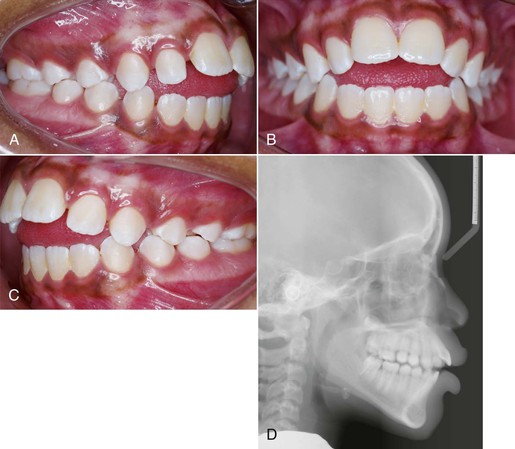

Figure 9-8 A–C, Patient with a finger-sucking habit resulting in an anterior open bite mesial to the first premolars. D, Lateral cephalogram showing characteristics of a dental open bite. E–H, Habit appliance with loops acting as a mechanical obstruction in close approximation to the anterior portion of the palate. I–K, Spontaneous correction of the anterior open bite after habit appliance delivery. L, Lateral cephalogram showing the open-bite closure. M, Superimposition reflecting the incisor extrusion that results with spontaneous closure of an anterior open bite with the habit appliance.